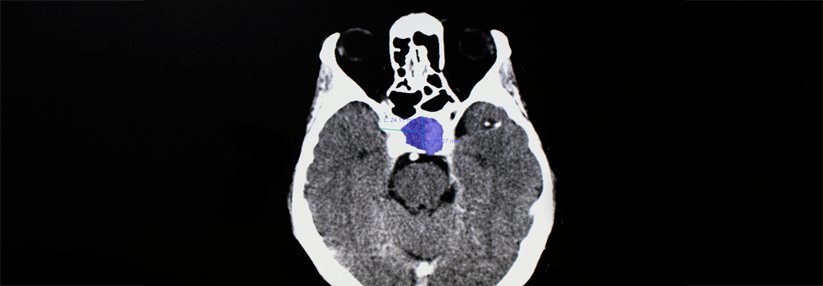

Im SRS-Mikroskop kann man gesundes Gewebe (links) gut vom Tumor (rechts) unterscheiden.

Im SRS-Mikroskop kann man gesundes Gewebe (links) gut vom Tumor (rechts) unterscheiden. © University of Michigan

Bei der SRS-Technologie gibt das Spektrum des reflektierten Lichts – die Raman-Streuung – Aufschluss darüber, ob es sich um dichtes Tumorgewebe oder gesunde Hirnsubstanz handelt. Das…